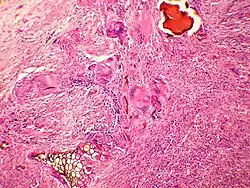

El estudio médico de los excrementos se conoce desde antiguo, llegándose incluso a la diagnosis a través de él. La escatología permite que se pueda determinar un rango bastante amplio de conocimientos sobre el animal que efectuó las deposiciones, como su dieta (y el lugar donde se ha alimentado), su grado de salud-enfermedad, así como la presencia de algunos parásitos intestinales.